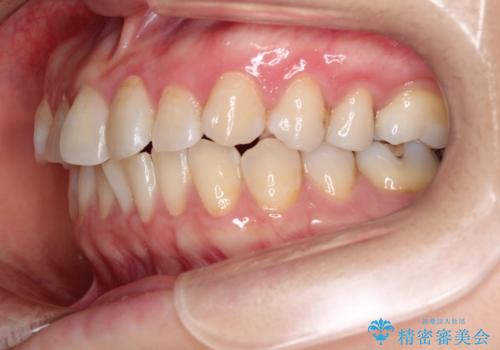

【インビザライン 】前歯の凸凹をなおしたい

- 前歯の凸凹を主訴に来院されました。

インビザライン にて治療を行い、歯並びが綺麗になったと満足していただきました。

前歯のガタガタの量が多かったため、IPR(歯のサイズを小さくするための処置)を行なって治療しました。